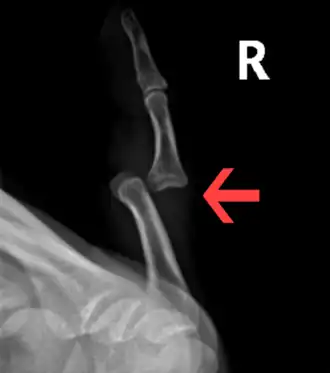

Prognosis varies depending on the location and extent of the dislocation. The prognosis of a shoulder dislocation is dependent on various factors including age, strength, connective tissue health and severity of the injury causing the dislocation.[23] There is a good prognosis in simple elbow dislocations in younger people. Older people report more pain and stiffness on average.[23] Wrist dislocations are often difficult to manage due to the difficulty in healing the small bones in the wrist.[23] Finger displacement towards the back of the hand is often irreducible due to associated injuries, while finger displacement towards the palm of the hand is more readily reducible.[23] Overall, recovering from a joint dislocation can range from a few weeks to months, depending on the severity of the injury.[4]

• Finger

• Interphalangeal (IP) or metacarpophalangeal (MCP) joint dislocations[41]

• In the United States, men are most likely to sustain a finger dislocation with an incidence rate of 17.8 per 100,000 person-years.[42] Women have an incidence rate of 4.65 per 100,000 person-years.[42] The average age group that sustain a finger dislocation are between 15 and 19 years old.[42]

• The most common dislocations are in the proximal interphalangeal (PIP) joints.[8]